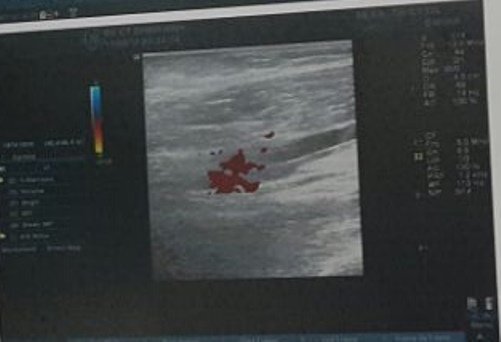

Bé theo mẹ đến công xưởng, không may bị băng chuyền sản xuất cuốn, bác sĩ phải bỏ 1/3 cánh tay phải để giữ tính mạng cho cháu.